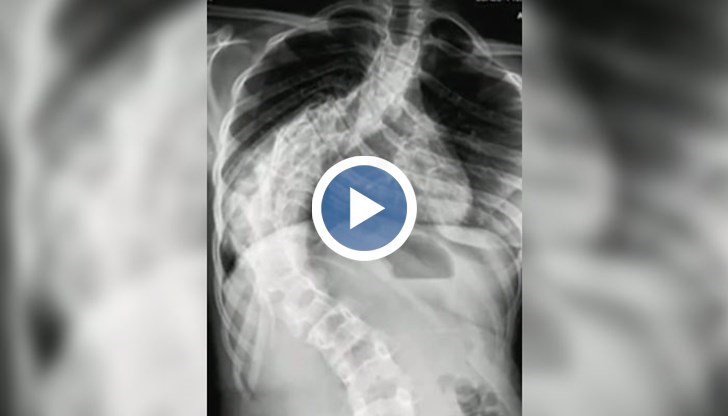

„Изкривяването беше 65 градуса. Аз се уплаших тогава и попитах дали не може да се коригира с корсет”, спомня си Иван, цитиран от Нова телевизия. Оказало се обаче, че не може. Две години по-късно изкривяването на гръбначния стълб на Илияна е 107 градуса.

Единственото решение е поставяне на специални импланти. Фондът за лечение на деца може да ги плати, но операцията се бави.